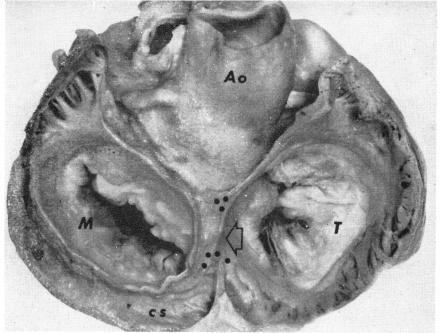

Cardiac innervation: anatomic and pharmacologic relations.